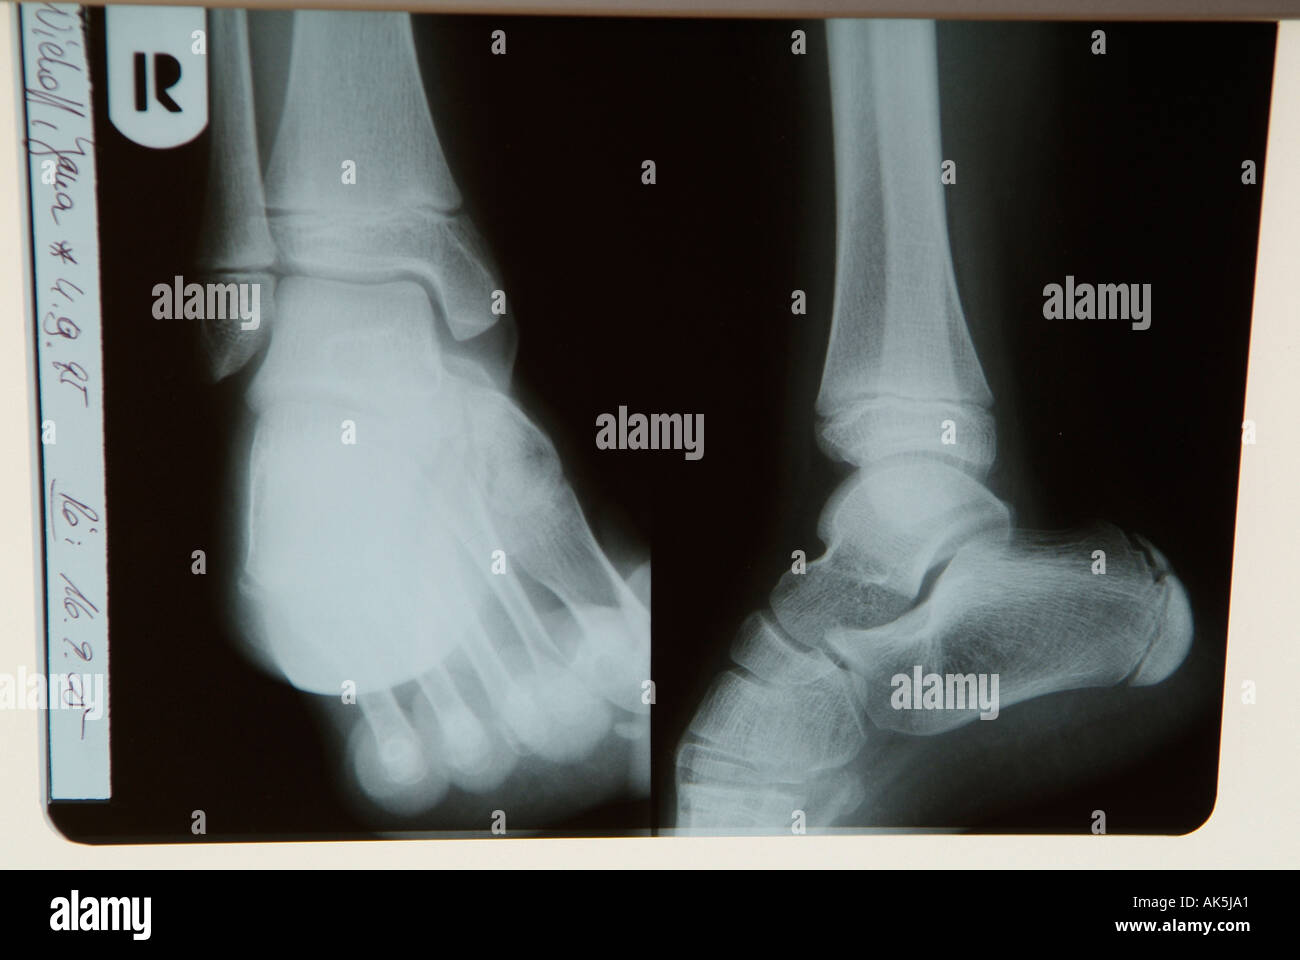

Xray normal human's foot lateral Stock Photo Alamy Normal Radiograph Of Foot 17 public playlists include this case. The image displays the soft tissues and bones of your. Several investigators have defined normal foot and. diographs are essential for successful foot and ankle deformity correction. this view demonstrates the location and extent of fractures in the foot, joint space abnormalities, soft tissue. 1 article features images from this case. . Normal Radiograph Of Foot.